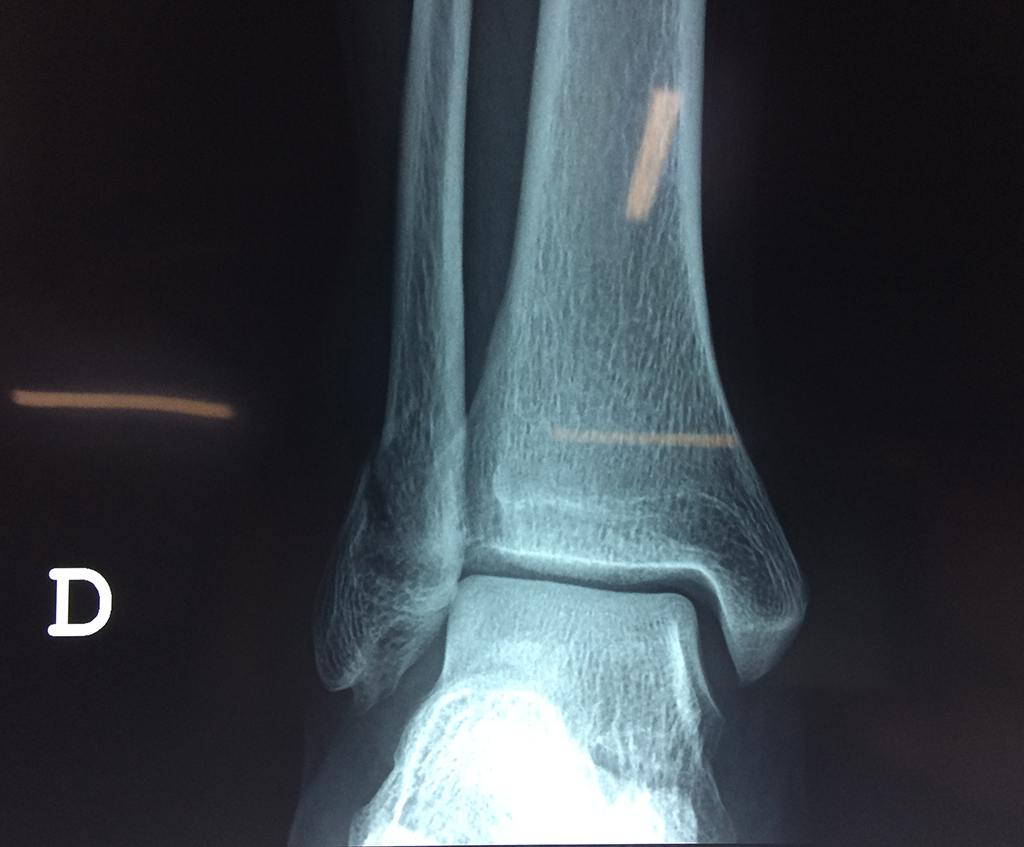

Una fractura de tobillo es la rotura de uno o más de los huesos del tobillo. Estas fracturas pueden ser:

- Parciales (el hueso está sólo parcialmente fisurado, no del todo).

- Completas (el hueso está perforado y está en 2 partes).

- Producirse en uno o ambos lados del tobillo.

Algunas fracturas de tobillo pueden requerir cirugía si:

- Los extremos de los huesos están desalineados entre sí (desplazados).

- La fractura se extiende hasta la articulación del tobillo (fractura intra-articular).

- Los tendones o ligamentos (tejidos que sujetan los músculos y los huesos entre sí) están rotos.

- El médico cree que sus huesos probablemente no sanen apropiadamente sin cirugía.

- El médico considera que la cirugía puede permitirle una recuperación más rápida y confiable.

- En los niños, la fractura involucra la parte del hueso del tobillo donde el hueso está creciendo.

Cuando se necesita cirugía, es probable que esta implique el uso de clavijas de metal, tornillos o placas para sostener los huesos en su lugar mientras la fractura se consolida. Los elementos de soporte pueden ser temporales o permanentes.